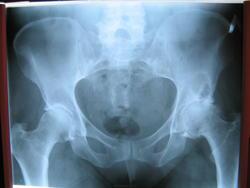

Пациентке около 45 лет, с жалобами на боли в тазобедренных суставах, поставили диагноз коксартроз и направили на рентгенографию. В анамнезе — хроническая почечная недостаточность. Чем могут быть вызваны данные участки просветления?

Снова возникли сложности. Это не метастазы, но возможно, это реактивный артрит или аваскулярный некроз головки?

Вероятно, это дегенеративные изменения с кистозными перестройками. Или киста в подвздошной кости.

С учетом расположения и анамнеза, ей срочно нужно сделать КТ или сцинтиграфию, поскольку это может быть и метастаз.

КТ, безусловно, необходима. Возможно, изменения различного характера — более крупное и овальное образование с тонким склеротическим ободком — это киста. А мелкие формирования, располагающиеся рядом, могут быть метастазами? Также на снимке виден участок остеосклероза в левой лонной кости.

Дефартроз, однако, признаков некроза головки не нахожу. В теле подвздошной кости видно многокамерное, окруженное склеротическим ободком кистовидное просветление с признаками периостита на этом уровне. (В его этиологии мне трудно разобраться)

В первую очередь я бы указал на кистозное образование, внешние контуры которого склерозированы.

Дефартроз, однако, я не вижу признаков некроза головки. В области подвздошной кости отчетливо видно многокамерное просветление, окруженное склеротическим ободком, с признаками периостита на аналогичном уровне. (Про его этиологию мне трудновато сделать вывод)

Этиология та же — артроз, в данном случае дегенеративно-дистрофическое поражение суставов с кистовидной перестройкой сочленяющихся костей

Дефартроз, Призноков некроза головки не нахожу. В теле подвздошной кости многокамерное,окружённое склеротическим ободком кистовидное просветление с признаками периостита на этом же уровне.( В этиологии его затрудняюсь)

Я бы в заключении первым делом указал на наличие метастаза. А в шейке правой бедренной кости и в краевых отделах крыла правой подвздошной кости показатели в норме?